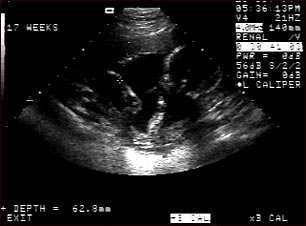

Ultrasonido de un feto normal; brazos y piernas

Ultrasonido normal a las 17 semanas de gestación. Las mujeres embarazadas pueden ver este tipo de imagen en la pantalla del ecógrafo y el técnico la puede imprimir. A la derecha aparece la cabeza, la equis señala el tobillo izquierdo y al centro de la pantalla se pueden observar la pierna y el brazo izquierdos del feto.